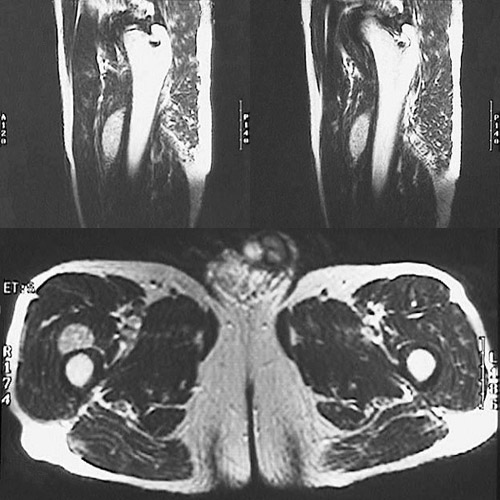

Click on the mass in the lower panel of the MRI scan above:

This is a magnetic resonance imaging (MRI) scan of the legs that reveals a circumscribed soft tissue mass arising in the thigh region just anterior to the femur (the fatty marrow is bright and the bone cortex is dark). Soft tissue tumors are difficult to diagnose. Though relatively small in size, this mass proved to be a sarcoma.